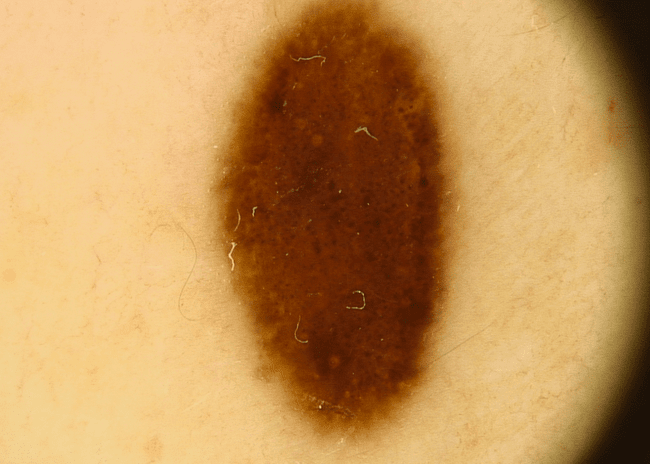

Zwykłe znamiona

Znane wszystkim zwykłe pieprzyki to inaczej znamiona barwnikowe powstałe w wyniku namnażania się komórek pigmentowych – głównie pod wpływem promieniowania UV. Większość z nich jest neutralna dla zdrowia i co najwyżej tworzy problem jako defekt kosmetyczny.

Zwykłe znamię barwnikowe - łagodny pieprzyk zdjęcie dermatologiczneZwykłe znamię barwnikowe - łagodny pieprzyk zdjęcie dermatologiczne

Zwykłe znamię barwnikowe - typowy pieprzyk zdjęcie medyczneZwykłe znamię barwnikowe - typowy pieprzyk zdjęcie medyczne

Zwykłe znamię barwnikowe - pieprzyk łagodny zdjęcie kliniczneZwykłe znamię barwnikowe - pieprzyk łagodny zdjęcie kliniczne

Zwykłe znamię barwnikowe - typowy pieprzyk zdjęcie dermatologiczneZwykłe znamię barwnikowe - typowy pieprzyk zdjęcie dermatologiczne

Zwykłe znamię barwnikowe - łagodny pieprzyk zdjęcie medyczneZwykłe znamię barwnikowe - łagodny pieprzyk zdjęcie medyczne

Zwykłe znamię barwnikowe - pieprzyk łagodny zdjęcie dermatologiczneZwykłe znamię barwnikowe - pieprzyk łagodny zdjęcie dermatologiczne